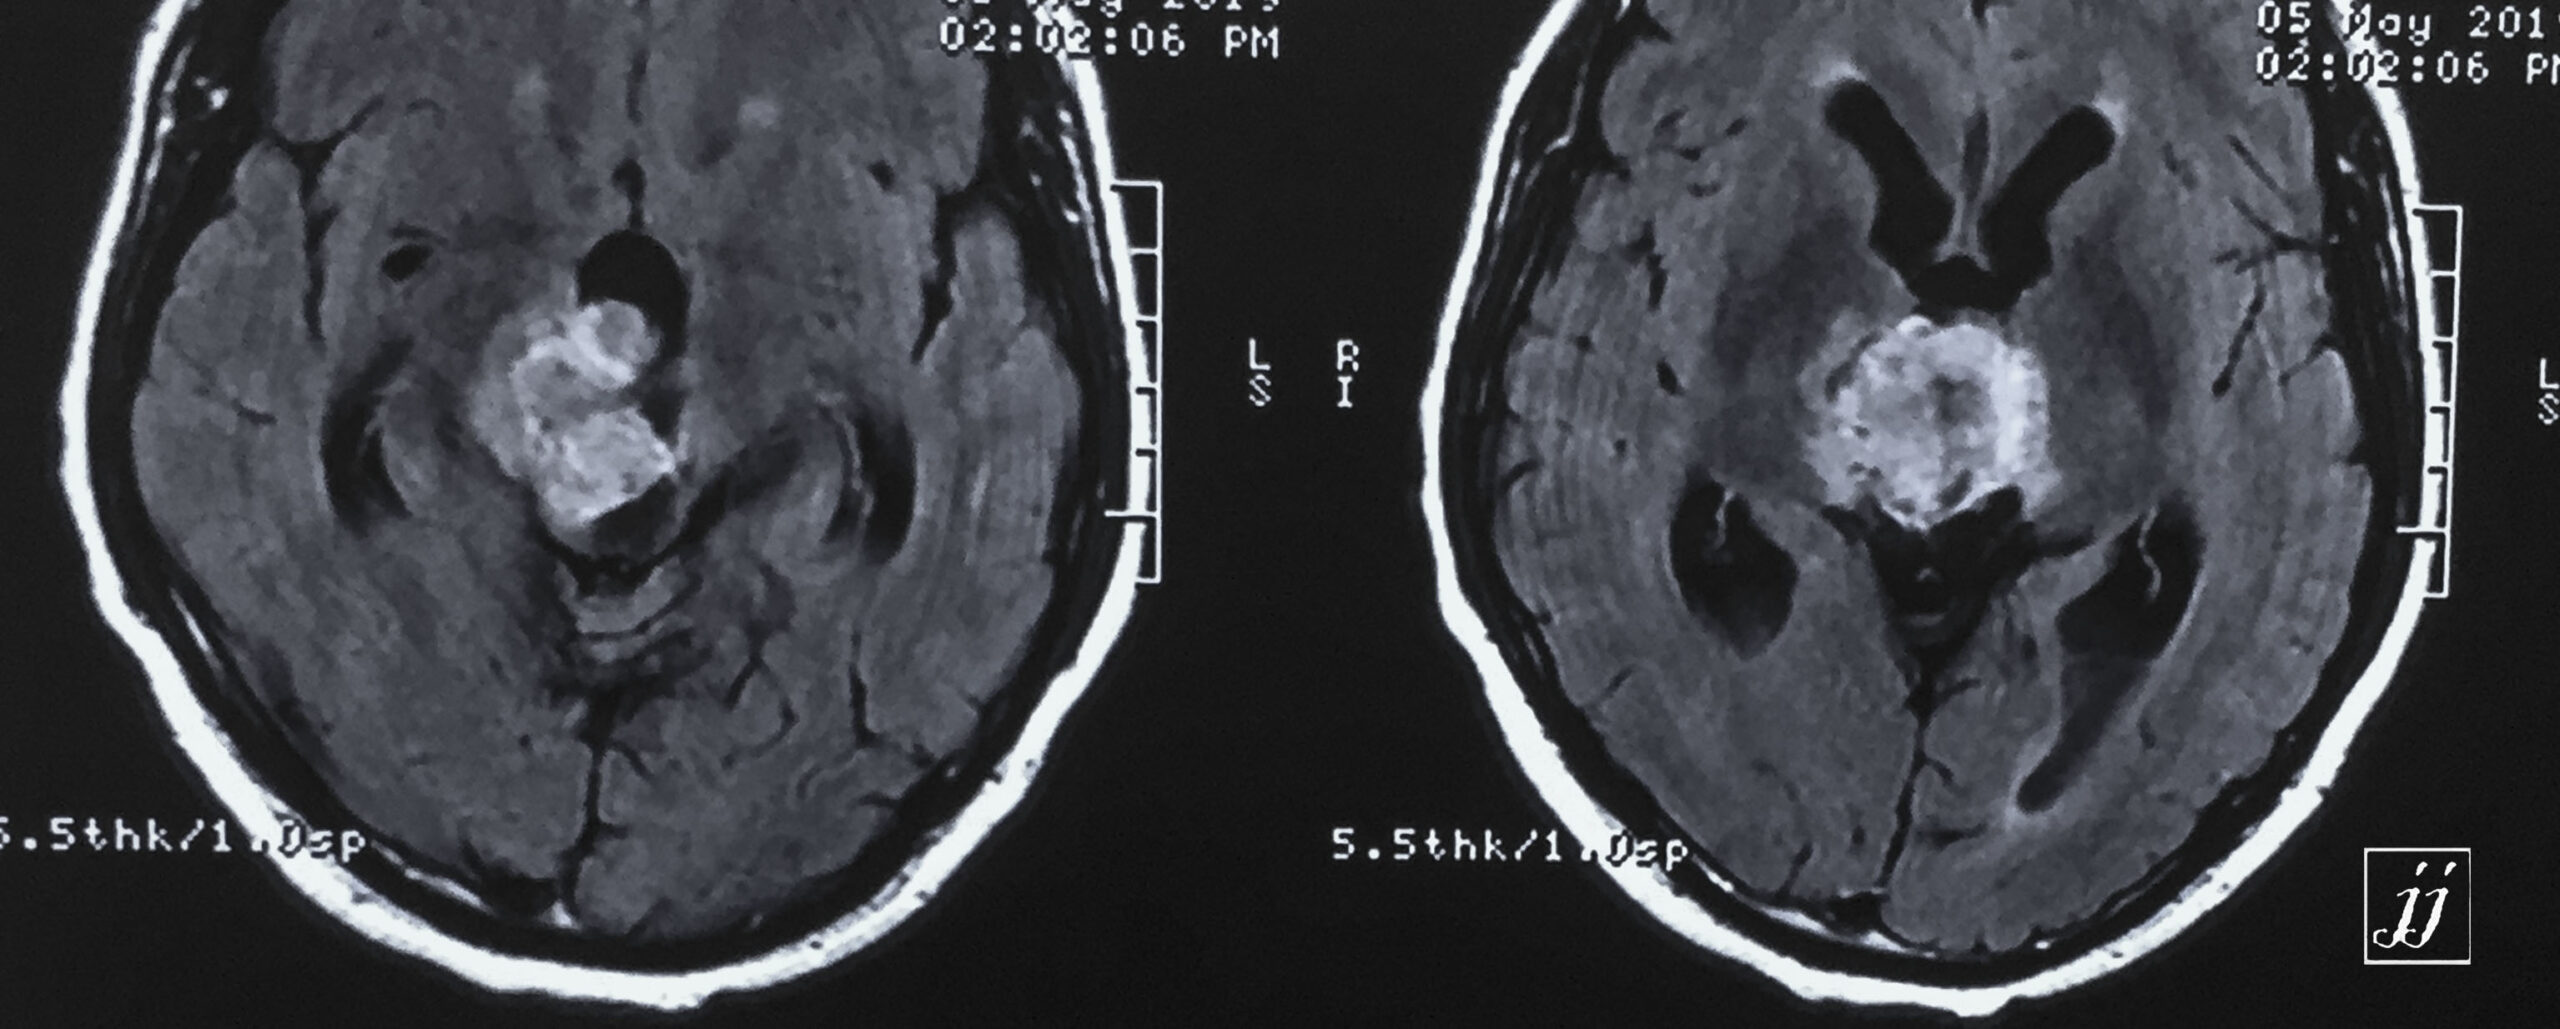

Brain- hugged size tectal and quadrigeminal meningioma (13)